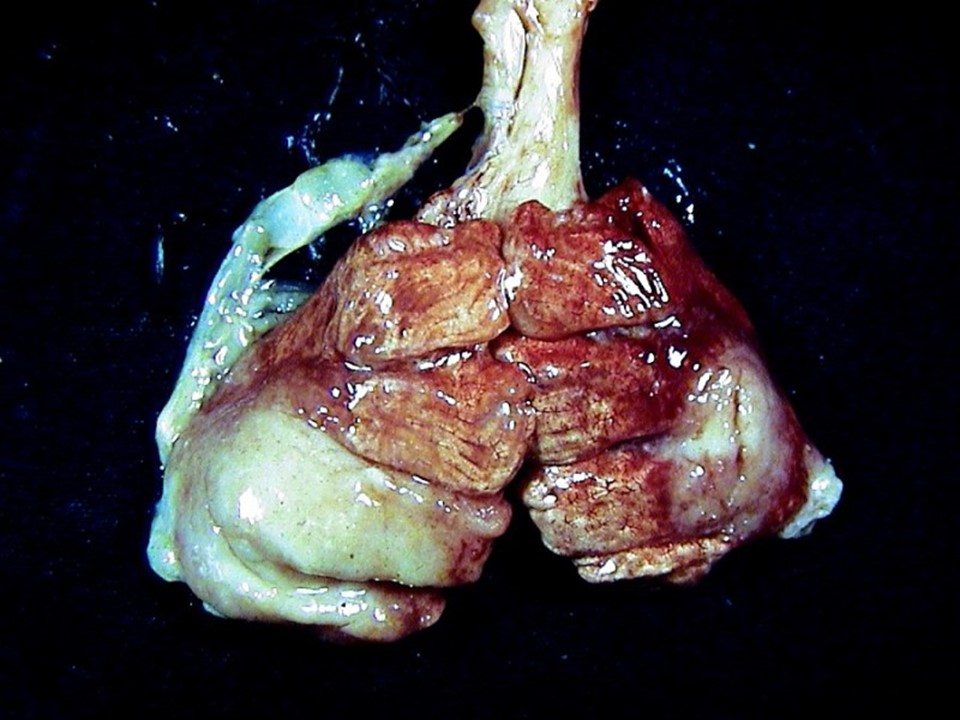

疾病中文名稱:馬立克病

疾病英文名稱:Marek's disease

作者:蔡信雄教授

影像說明:翼神經受侵犯而翅膀下垂,坐骨神經受侵犯呈劈腿狀